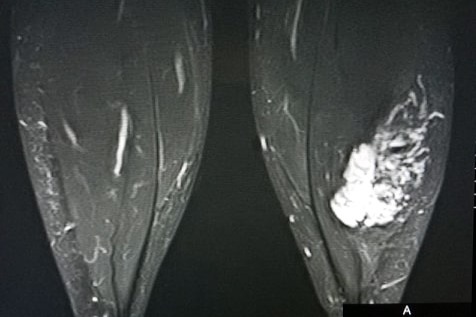

This is what Allison's FAVA lesion looks like on MRI

The white marbled areas will be removed.